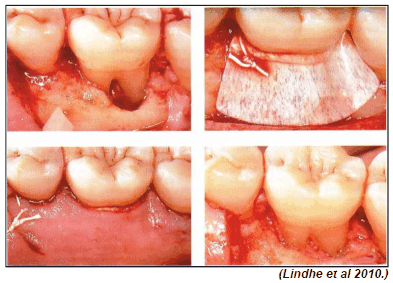

Observe a imagem a seguir.

A técnica cirúrgica mostrada na figura é mais indicada para qual tipo de defeito de furca?